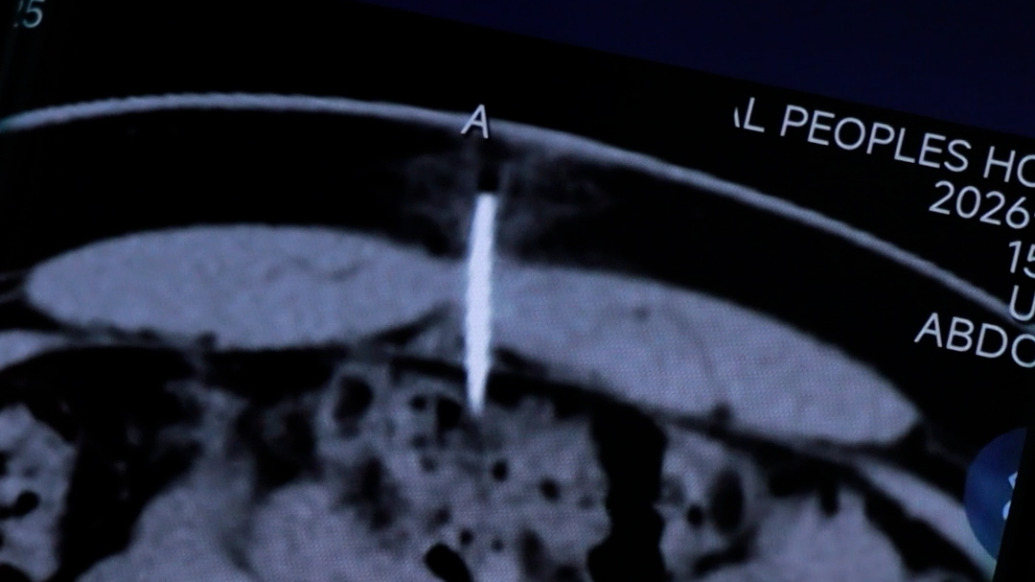

3月30日,河南新乡。一名15岁男孩因腹痛就诊,被发现一根长约四五厘米的缝衣针从肚脐上方扎入腹腔壁,距肠管极近,伴有烫伤疤痕。男孩自述系模仿游戏、视频行为所致。经河南医药大学第一附属医院小儿外科手术取出后,男孩已康复出院。